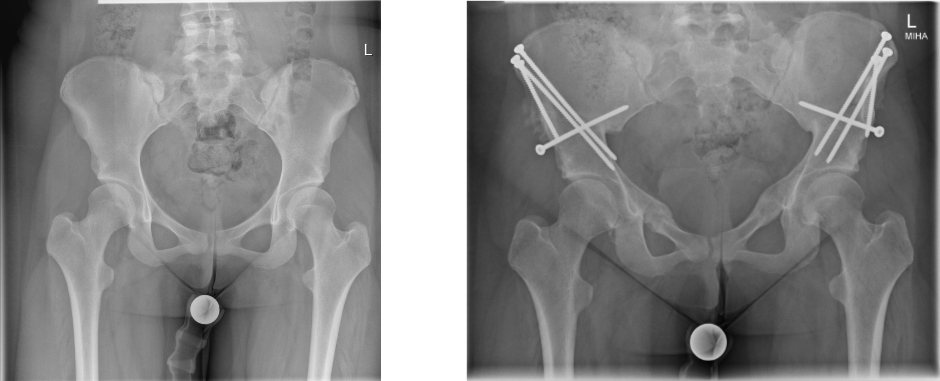

Die operative Therapie der Pfannendachdysplasie zielt auf eine Reduktion der Druck- und Scherbelastung des knöchernen und weichteiligen Pfannenrandes. Hierzu führen wir eine Dreifach-Beckenosteotomie (die sog. Triple-Osteotomie nach Tönnis und Kalchschmidt) durch, bei der die Hüftgelenkspfanne aus dem Beckenknochen durch drei „Knochenschnitte“ herausgelöst, in eine biomechanisch günstigere Position gedreht und in dieser mit Schrauben fixiert wird. Dieser Eingriff zieht eine verbesserte Hüftkopfüberdachung nach sich.

In besonders gelagerten Fällen muss dieser Eingriff mit einer sog. intertrochantären bzw. subtrochantären Osteotomie, einem „Knochenschnitt“ am Oberschenkelknochen, verknüpft werden, um eine noch günstigere Biomechanik für das betroffene Hüftgelenk zu erzielen.